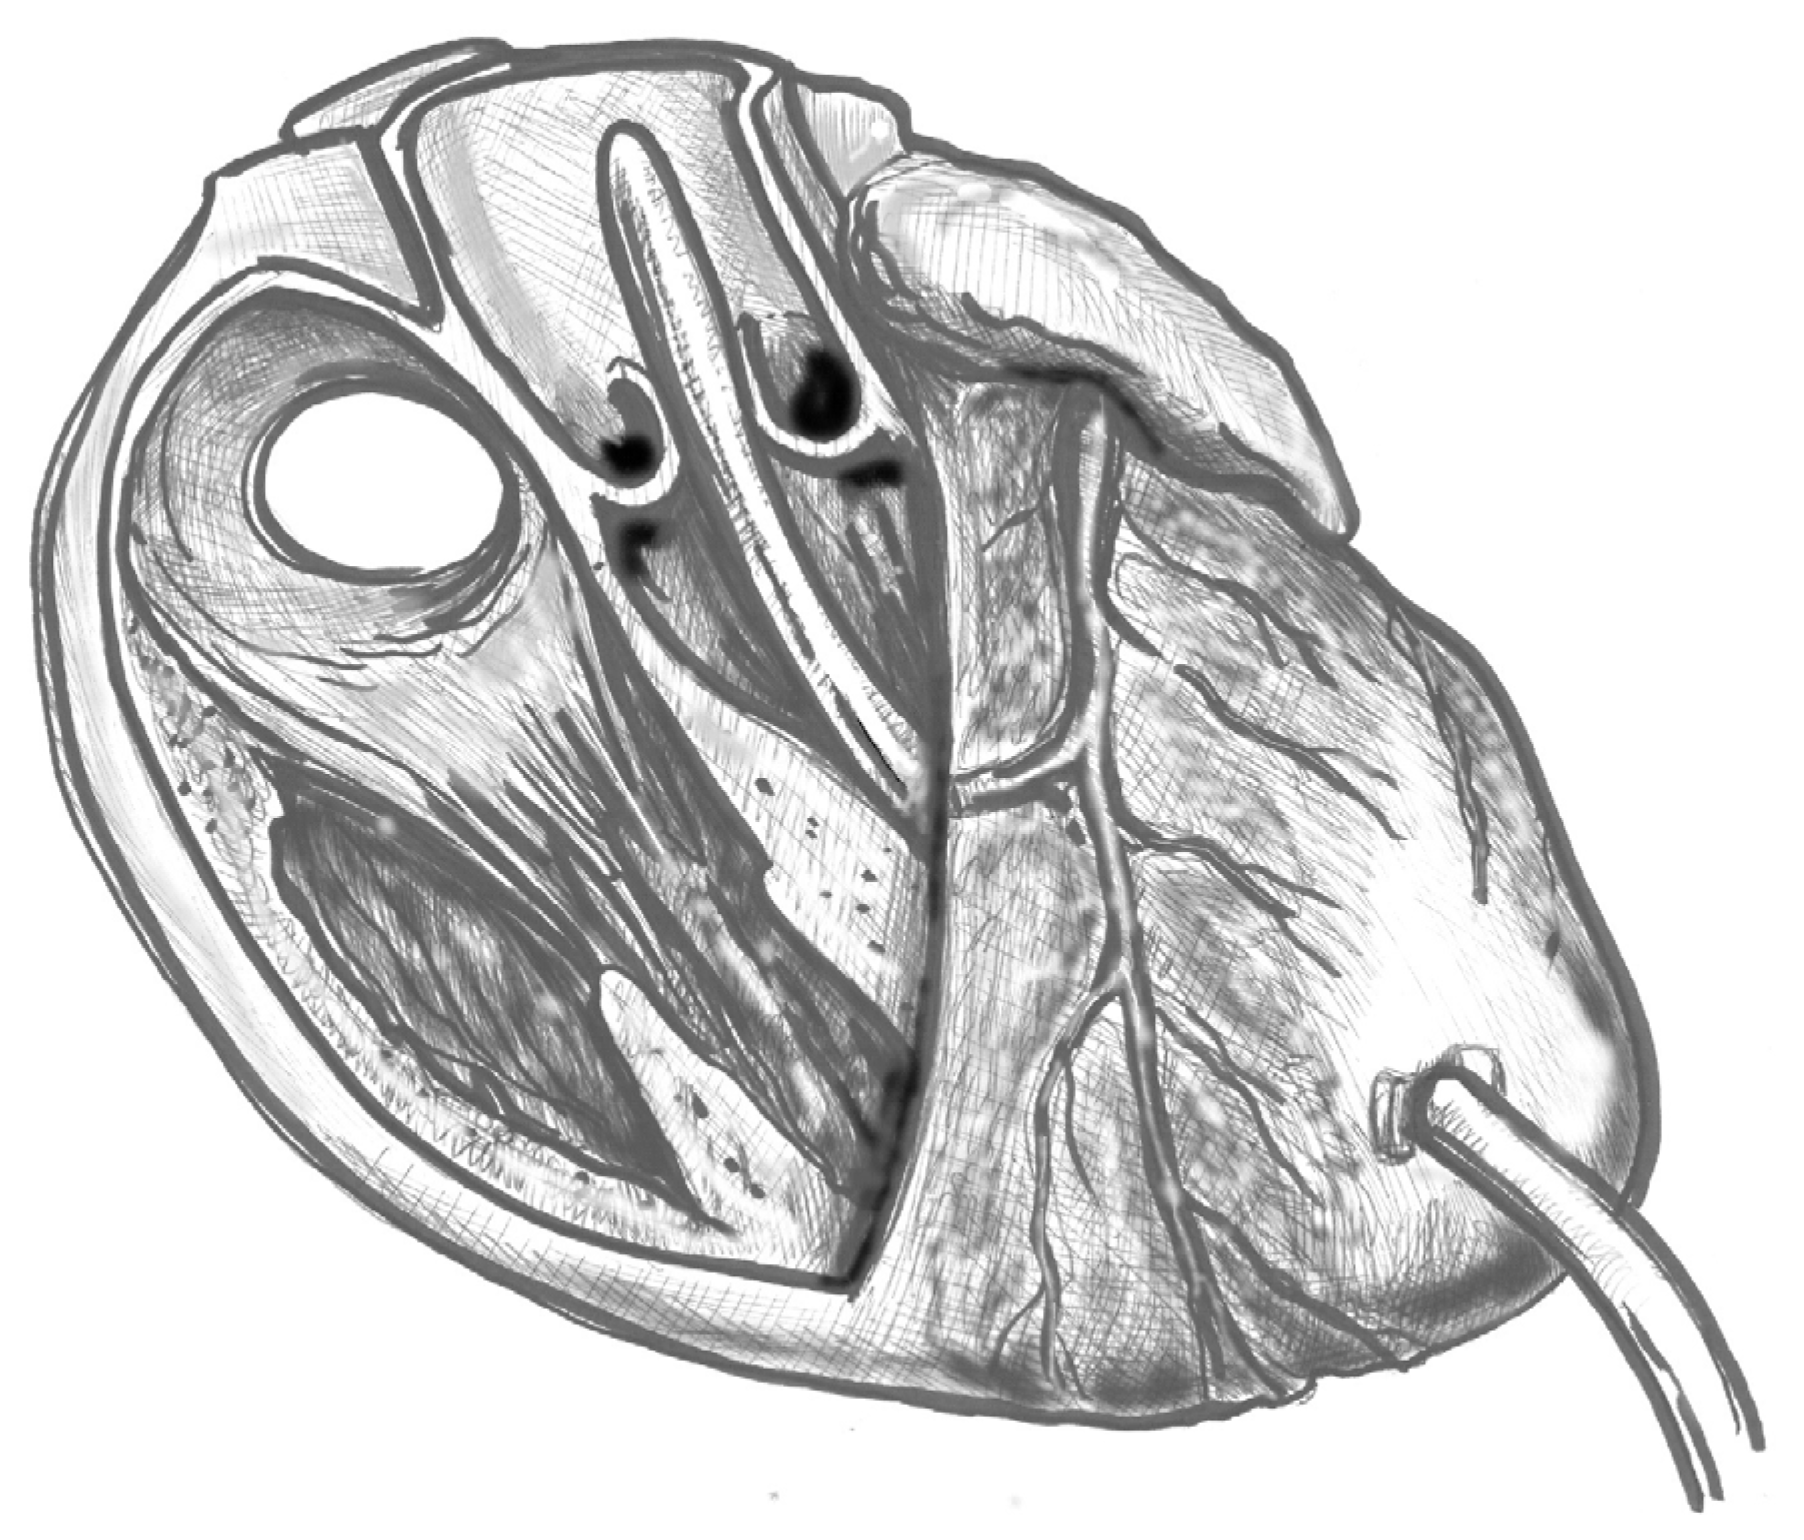

- Figure 3. Gently advance the cannula along the LVOT axis towards the ascending aorta under continuous TEE guidance. Fix the cannula in place using two transmural prolene 2-0 sutures with pledgets and tourniquets.